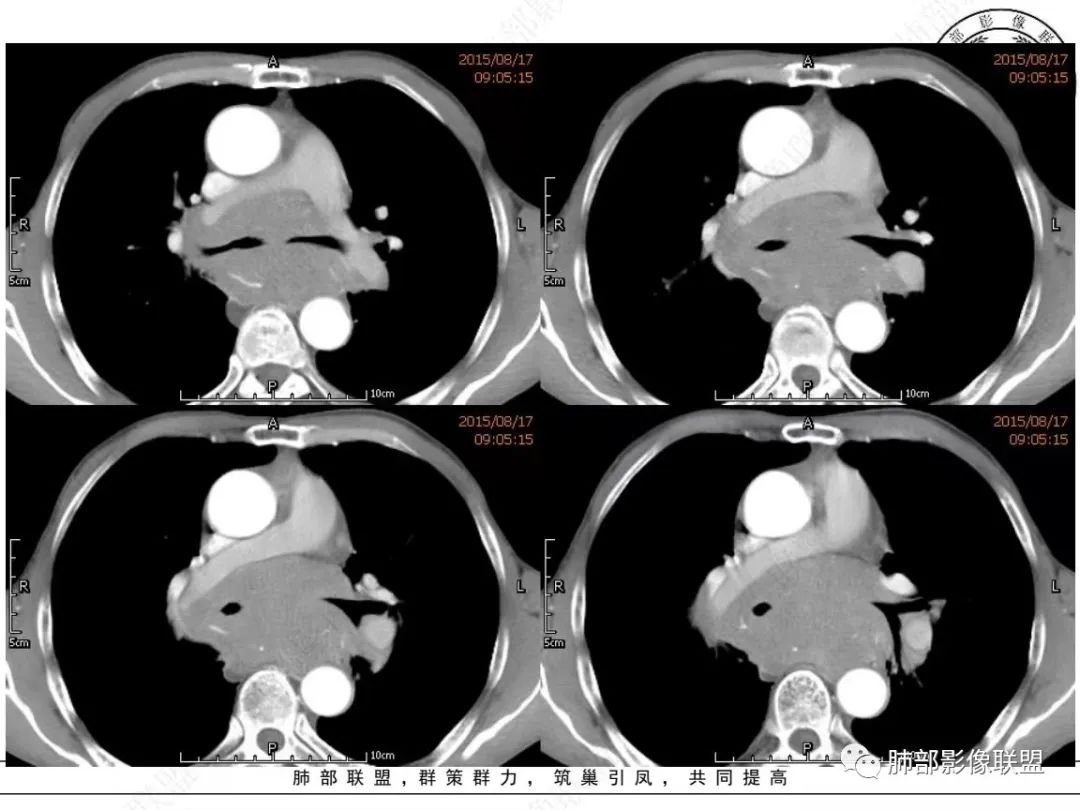

我想CT上,侵袭力强也是特征,破坏力弱表现在血管包绕但形态基本不变,和比较软的感觉。

另外小细胞癌中央区肿块通常没那么圆,有鸭蹼状凸起,周围也不是特别干净,常有小结节或其它阴影

MCL的CT表现为分布无规律的全身多区域淋巴结受侵,少有单一区域淋巴结受累,结外器官受侵多见;MCL有一般NHL淋巴结受累基本CT表现,平扫CT表现为病变密度均匀,受累淋巴结区内呈融合状生长,边界清楚,增强后病灶呈均匀、中等强化,一般病变内无低密度坏死区。确诊需要病理及免疫组化,根据肿瘤组织形态学和免疫组织化学 CD5 及cyclin D1 的表达绝大多数 MCL 可做出明确病理诊。

1.小细胞肺CA:好发吸烟老年男性。常有血液NSE及胃泌素释放肽前体升高。Syn、CgA、CD56阳性。其CT特点可有:冰冻纵隔、冰冻肺门。血管包埋征。针尖样支气管。鸭蹼状凸起。娘小崽大。脂肪间隙消失(常指纵隔及肺门内)。阻塞性炎症不重。侵袭性强。破坏力不强。收缩力弱,内无空泡。沼泽样强化,坏死散而小,坏死不彻底,强化偏低。表面圆钝,角状及条状凸起,蠕虫样表现,腊肠样尾巴(朝肺门侧或背离肺门侧均可以)。胸水多“清澈”(可以理解为淋巴液回流障碍导致的胸水)。点簇状钙化(类似盐与胡椒样)。多见癌性淋巴管炎。另外黄勇老师提出胸膜下的小细胞肺癌具有“山丘征”的特点。